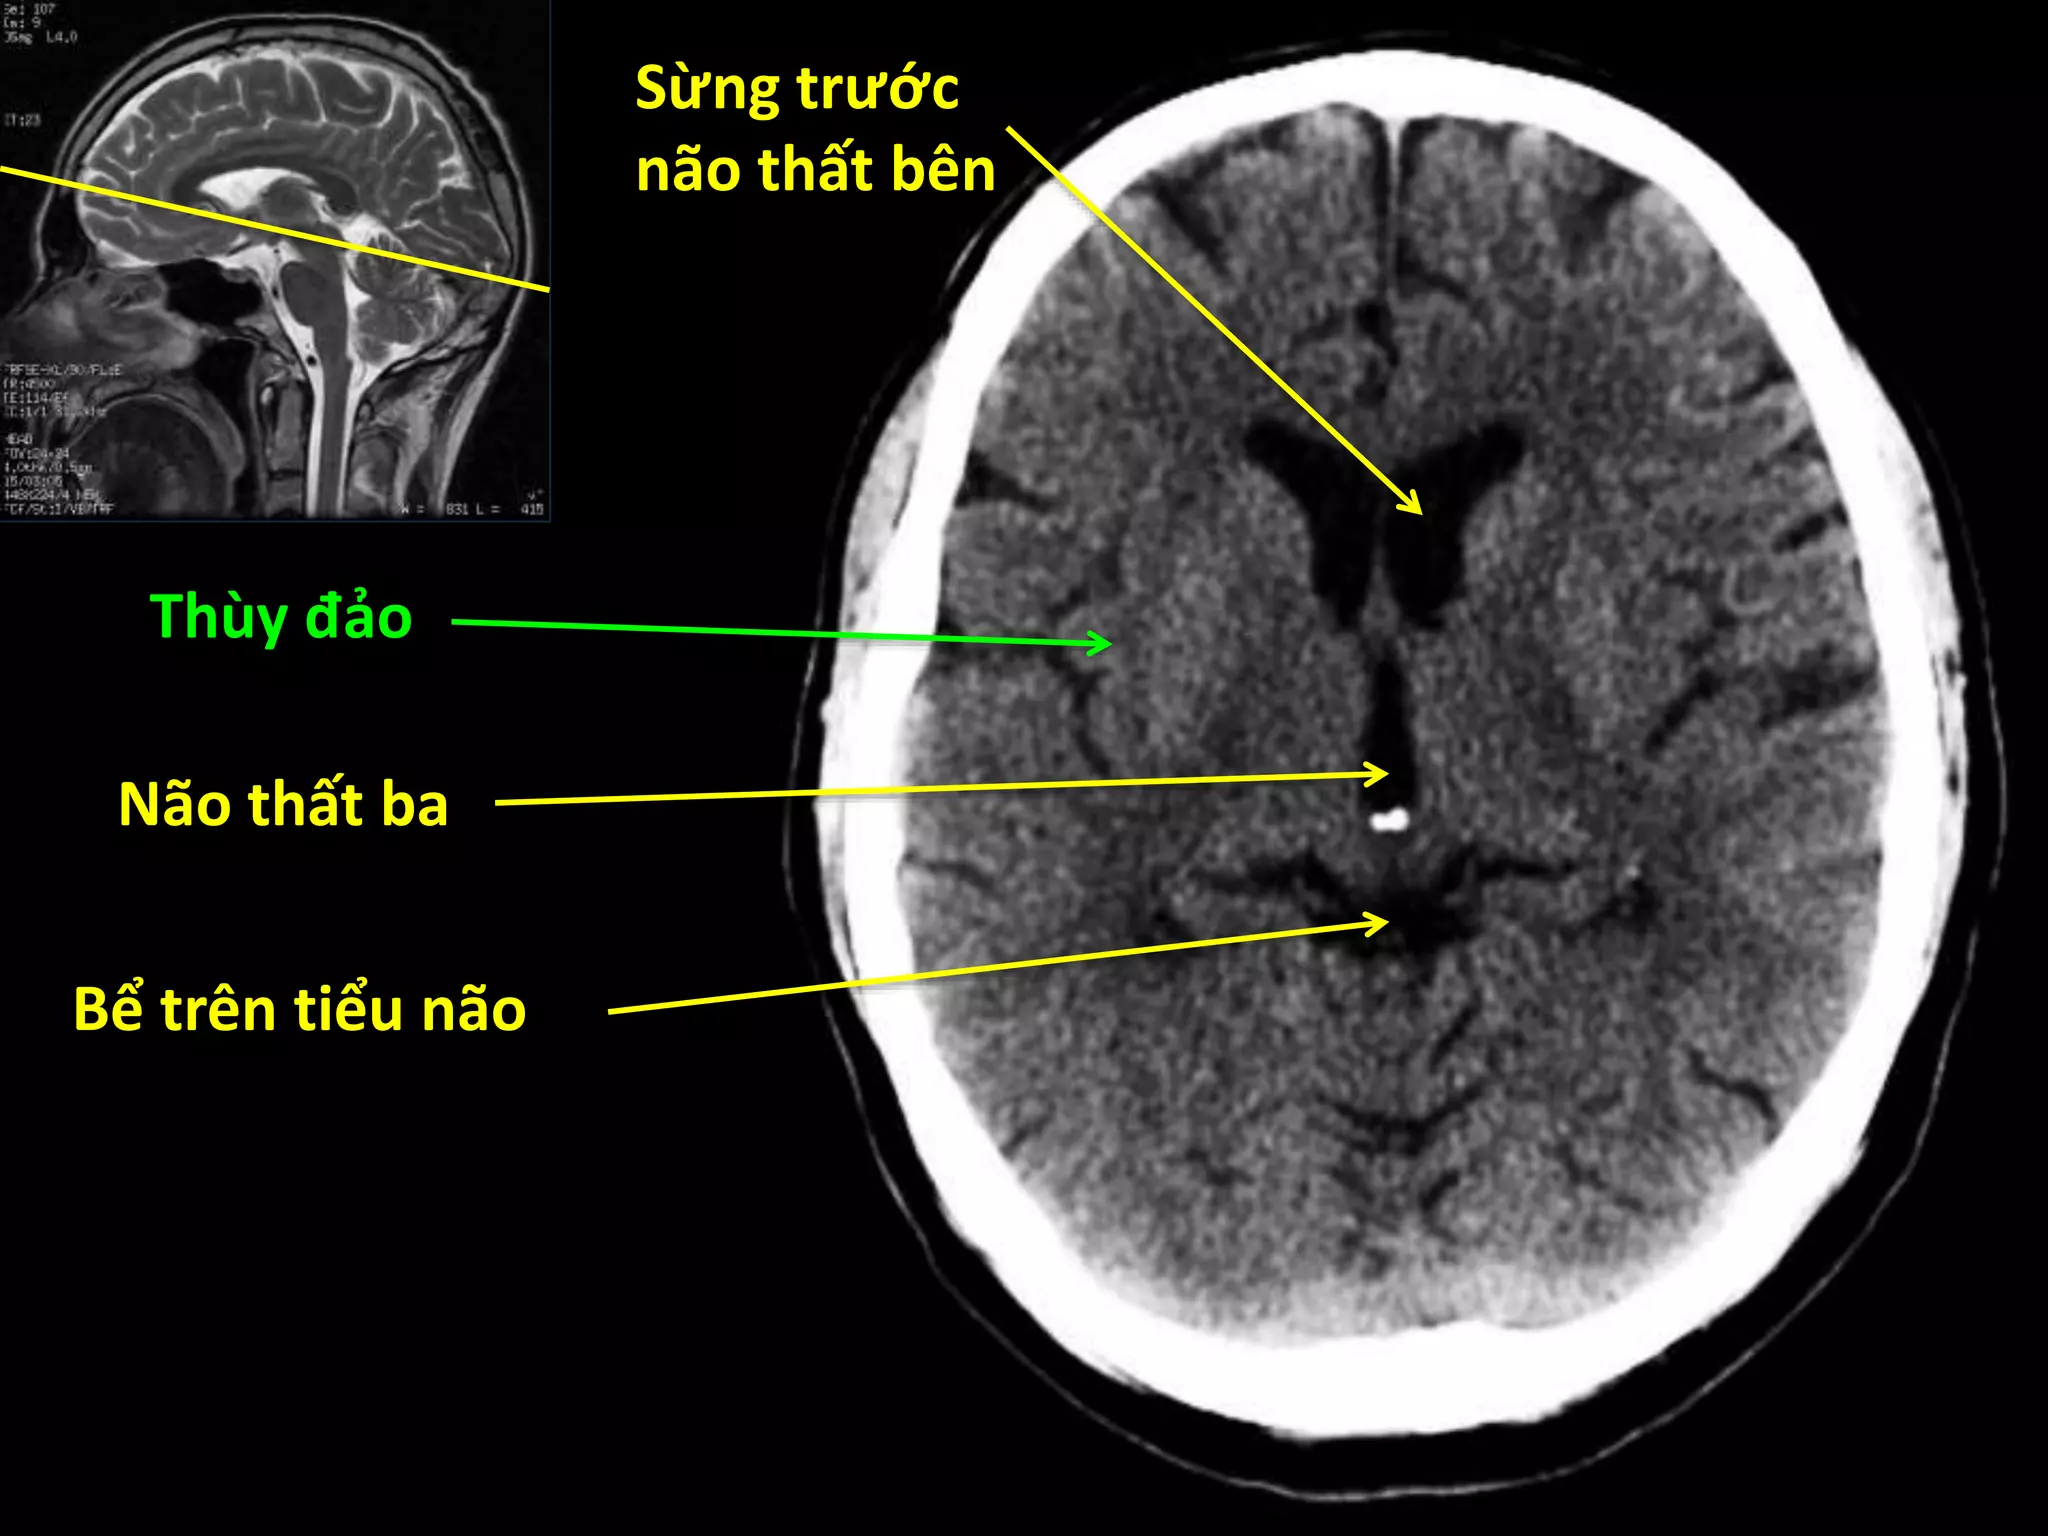

Sừng trước

não thất bên

Thùy đảo

Não thất ba

Bể trên tiểu não

Đầu nhân đuôi

Đồi thị

Nhân bèo

Bao trong

Bèo sẫm

Cầu nhạt

Cánh tay trước

Thùy trán

Thùy thái dương

Tiểu não

Cầu não

Não thất tư

Bể trên yên

Khe Sylvius

Hành não

Sừng trước não thấtbên Thùy đảo Não thất ba Bể trên tiểu não